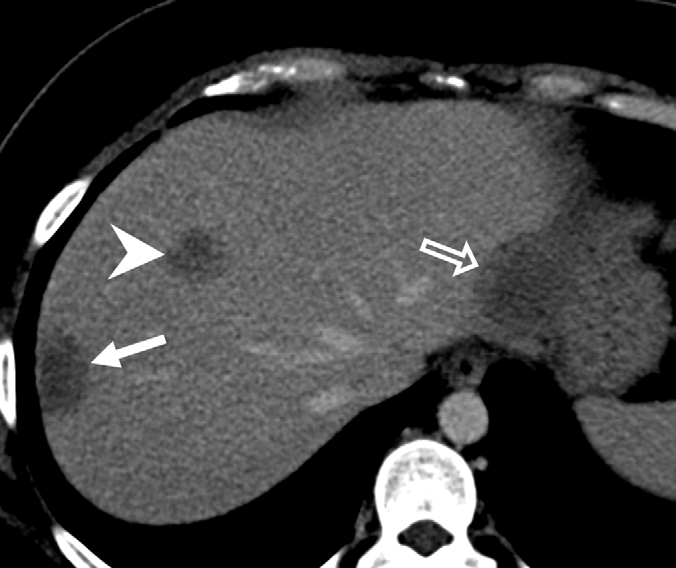

- 中年女性无症状肝脏多发病灶,原因为何? 医脉通-临床病例平台患者女,45岁,因影像学检查偶然发现肝脏多发病灶就诊。患者无相关症状,体格检查正常。……